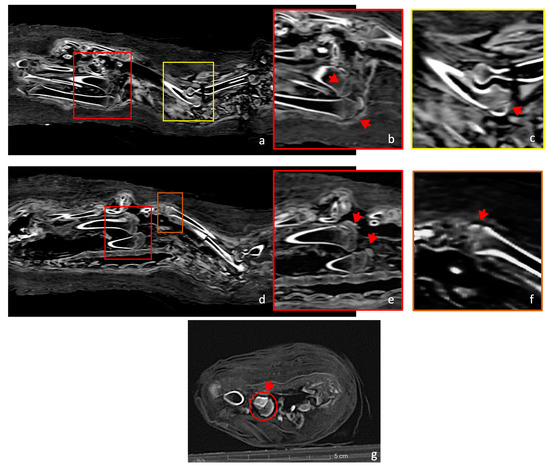

Several significant fractures were present in the postcranial skeleton. The forelimbs were damaged; the left humerus had a dislocation in the proximal epiphysis, the left ulna and radius showed a break in the middle of the diaphysis (Figure 6a), and the right humerus had three separate fractures: a dislocation in the proximal diaphysis, a detachment of a shrapnel fragment that moved into the medullary cavity, and a separation of the distal part of the bone (Figure 6b).

Figure 6.

Coronal view of specific fractures in the cat skeleton. (a) The red arrow indicates the fractures of the left ulna and left radius (left side). (b) Three fractures of the humerus are marked by red arrows: (from left to right) a fracture of the distal epiphysis; the presence of a shrapnel fragment in the humerus; and a 90-degree dislocation and rotation of the proximal head.

The central part of the body was severely damaged, with all the ribs and several vertebrae displaced from their normal positions. The last cervical vertebra (C7) and the thoracic vertebrae were completely fragmented, while the remaining cervical, lumbar, and caudal vertebrae had experienced less damage and remained in their correct positions (Figure 7a). The first ribs were visible and showed minimal fracturing, even though they appeared rotated by 180 degrees (Figure 7b), contrarily to the other ribs, which were extensively damaged.

Figure 7.

In the coronal view (a), the skeleton shows the cervical and lumbar vertebrae correctly positioned (highlighted by yellow arrows). However, the thoracic vertebrae are severely dislocated and fragmented. In the axial CT scan (b), attention is drawn to two first ribs that are rotated 180 degrees from their normal position (highlighted by red arrows).

Most of the postcranial elements have evident fractures, such as those indicated in Figure 4. The breaks on the limb bones seem to have occurred post-mortem, unlike the fractures on the skull and vertebrae. For example, the proximal part of the humerus is separated and rotated by 90 degrees in relation to the bone’s diaphysis (Figure 6b). The manipulation, embalming process, and positioning of the skeleton may have compromised the structural integrity of the bones, as did its burial and subsequent transport, since there is no evidence for bone repair/growth.